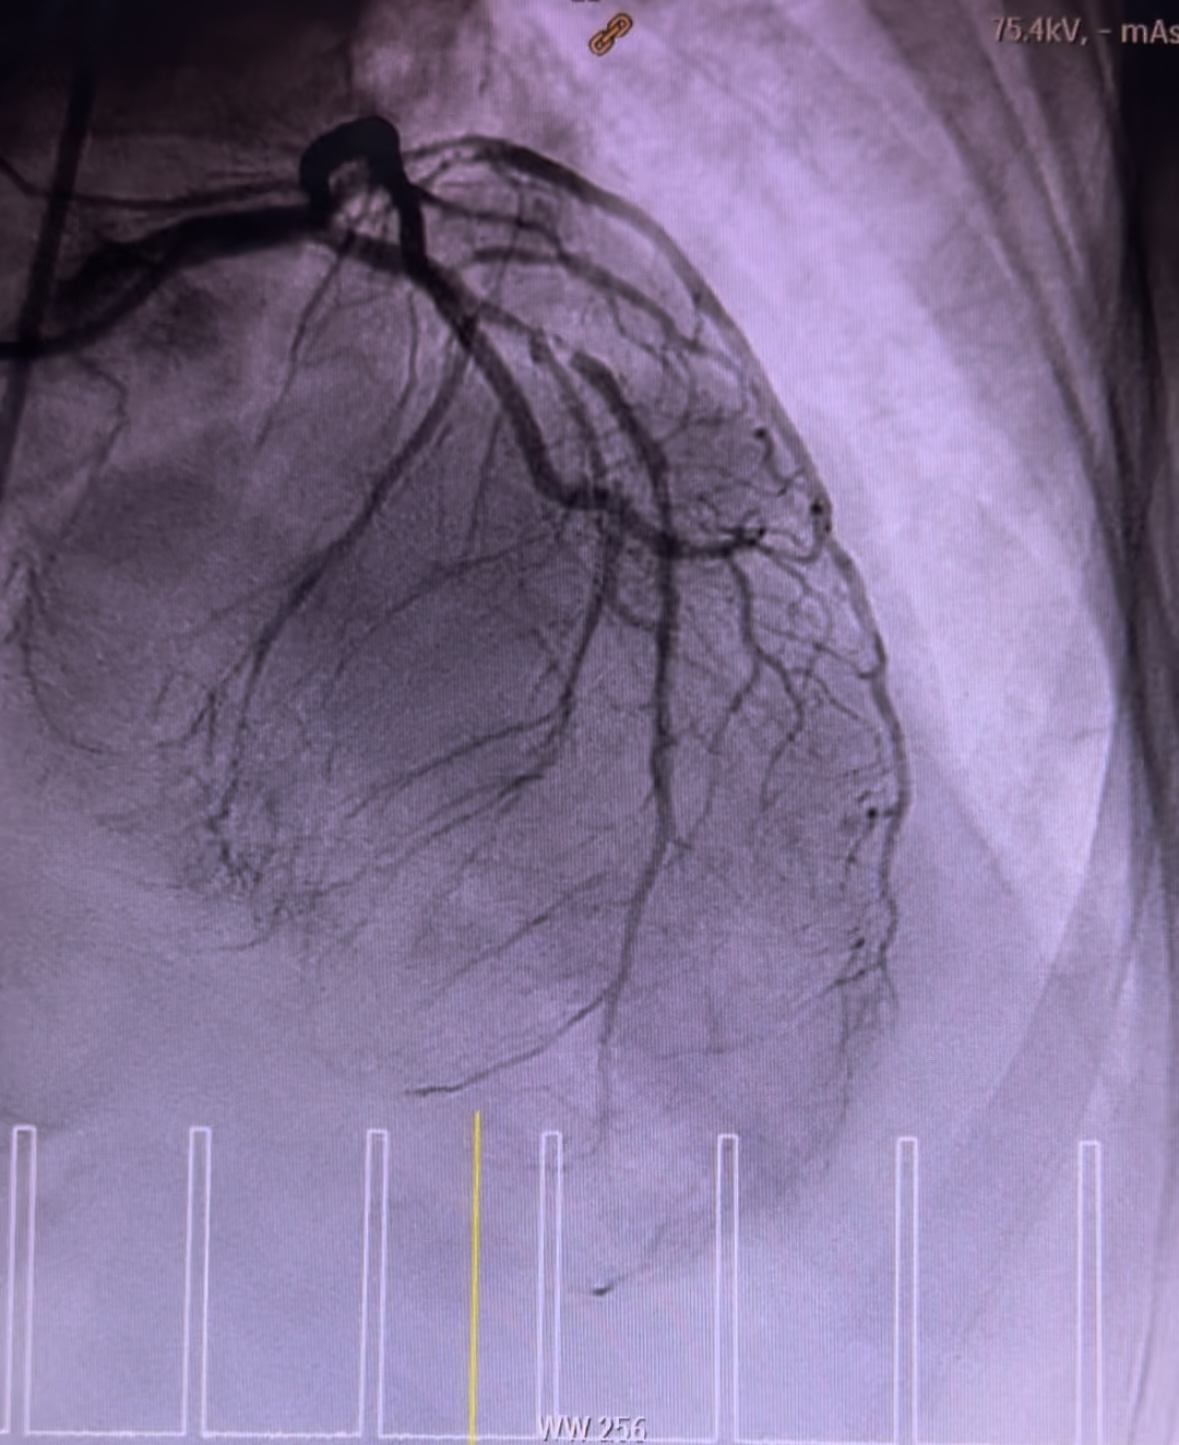

Coronary angiogram demonstrated smooth left main, 90% stenosis in the proximal left circumflex, 99% focal stenosis with severe calcification at mid LAD, followed by mild diffuse plaque until the distal end, and 90% stenosis at ostial D1. Right coronary was calcified with 80% stenosis at the proximal segment, 90% stenosis at the mid segment, and CTO at the distal segment. Discussion was held with cardiothoracic surgeons in which CABG was viewed incompatible.